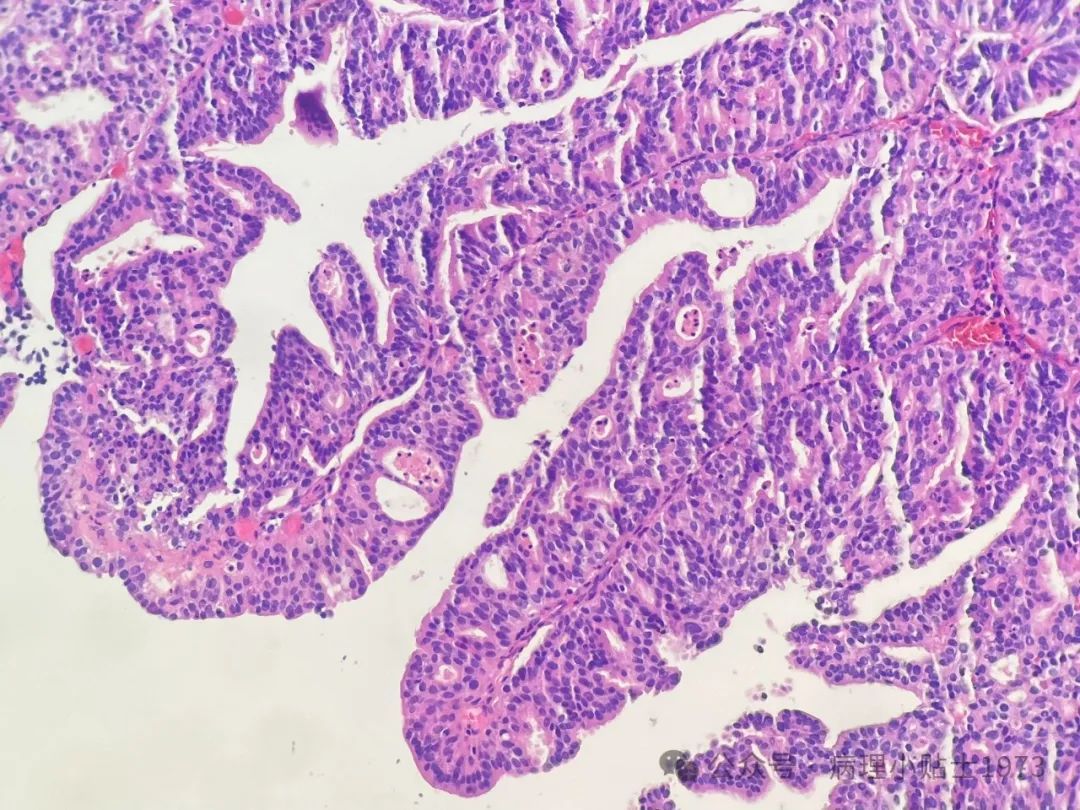

- 参考ISUP新分级系统: 国际泌尿病理学会(ISUP)提出了新的3级分级系统,并对含有高级别成分的非浸润性乳头状尿路上皮癌的诊断标准进行了讨论。例如,ISUP建议对于高级别成分占比在5%-50%的病例,诊断为低级别伴高级别成分,并注明比例;≥50%则直接诊断为高级别。WHO 2022则以5%为界限区分低级别伴局灶高级别成分和高级别。

- 综合判断: 结合本例广泛的腺样分化、免疫组化特征(p16, CK20, Ki67)以及细胞学特点(灶区核仁清晰、凋亡易见),尽管形态上可能未完全达到WHO标准的高级别,但根据ISUP分级,倾向于将其归入高级别非浸润性乳头状尿路上皮癌 (G2)。

四、病理切片注解图示

以下图片进一步展示了病理诊断的关键特征: